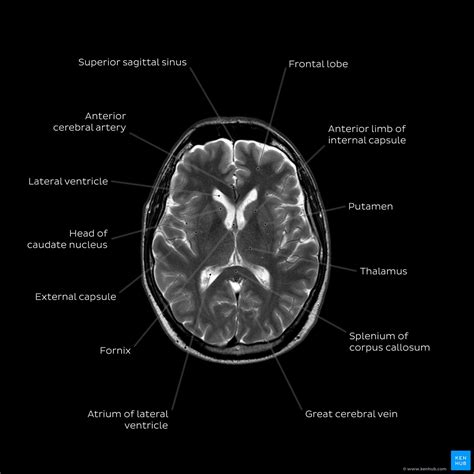

Web preparation during the scan how to cope with the mri experience results learning that you need to undergo a magnetic resonance imaging (mri) test can be intimidating. The 2 series you will want to pull up next to each other are the dwi (diffusion weighted image) & adc (apparent diffusion coefficient). Web mri brain is a specialist investigation that is used for the assessment of a number of neurological conditions. It is the process by which magnetic fields & radio waves lead to the generation of a detailed image of your brain structures; For mr brain it’s useful to look at t2, then flair, then dwi/adc, as this will help distinguish between most differentials). Web how to read brain mri. Brian gay provides an easy to understand explanation of an mri brain scan and how to read it. First look mri can provide a video report created by our experienced. Compare the mri images to other imaging modalities (e.g. Although rarely needed to evaluate sleep disorders, it may be used to assess stroke (a potential cause of central sleep apnea) or even epilepsy (which may cause.

Brain mri examination should follow a systematic approach starting from the midline and going laterally. Although rarely needed to evaluate sleep disorders, it may be used to assess stroke (a potential cause of central sleep apnea) or even epilepsy (which may cause. Web how to read brain mri. Web an mri of the brain is the most commonly performed medical imaging test in 2022. Web how to read a brain mri in this post, let’s take a look at the basics of how to read a brain mri, because it often can’t wait until the radiologist gets in in the morning. Brian gay provides an easy to understand explanation of an mri brain scan and how to read it. The initial portion will contain demographic information, which will allow anyone looking at the report to identify the patient as well the location where the study was performed. Compare against other imaging modalities. Compare the mri images to other imaging modalities (e.g. Next will be a brief description of the exam performed (for example, “mri brain w/o contrast”) and the date. First, acute ischemic stroke (ais).